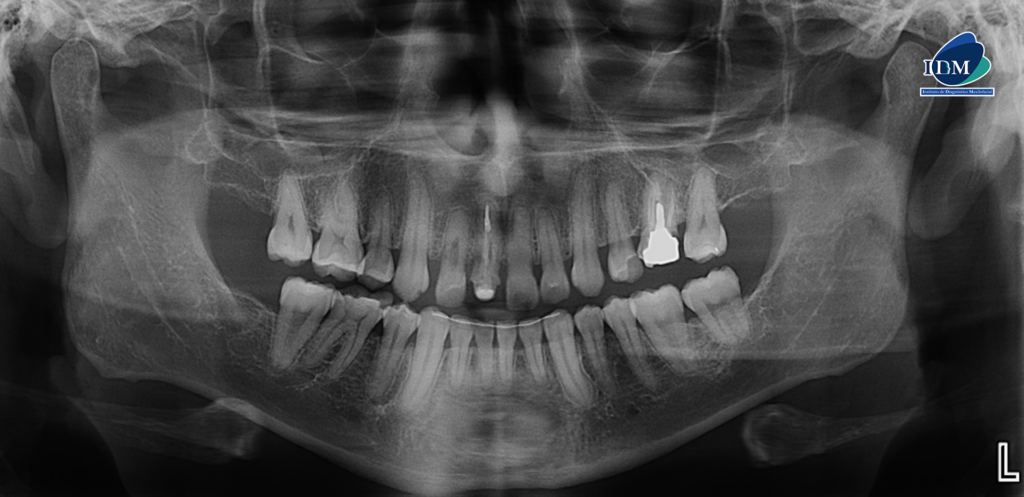

En la radiografía panorámica (Figura 1), se aprecia imagen radiolúcida en pared radicular distal en tercio cervical y obliteración en tercio apical de pieza 12, imagen radiolúcida en pared radicular distal en tercio cervical de pieza 11, obliteración de conducto radicular en pieza 21.

Radiografia Panorámica